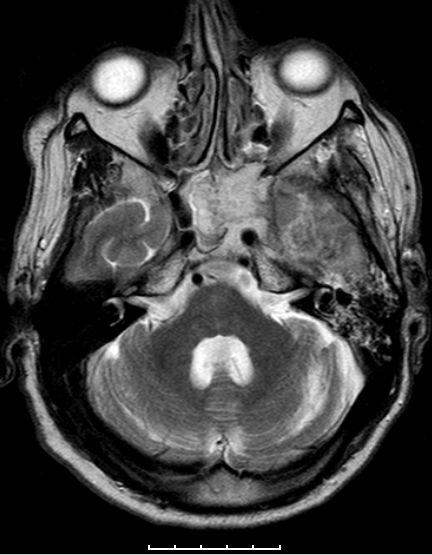

Glioblastome metastasieren normalerweise nicht außerhalb des ZNS. | |

| Fall | Im vorliegenden Fall kam es während der Temodal-Therapie nach postoperativer Radiochemotherapie zu einen Durchbruch des GBs durch die Schädelbasis. | |